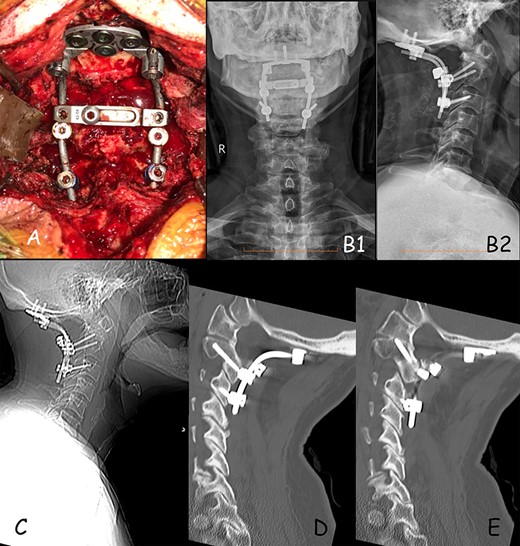

(A) Intra-operative positioning of occipital plate and screws construct. (B) 1-month post-op X-ray, (B1) anterior–posterior and (B2) lateral X-ray. (C) 12-months post-op lateral X-ray showing good positioning of construct. (D) Sagittal CT demonstrating good positioning of construct on the right side. (E) Sagittal CT demonstrating good positioning of construct on the left side.